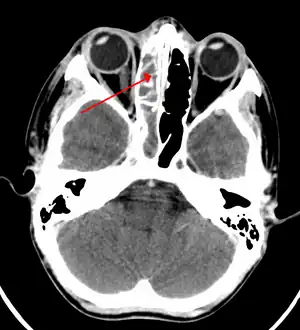

| A CT scan showing sinusitis of the ethmoid sinus | |

For sinusitis lasting more than 12 weeks, a CT scan is recommended.[47] On a CT scan, acute sinus secretions have a radiodensity of 10 to 25 Hounsfield units (HU), but in a more chronic state they become more viscous, with a radiodensity of 30 to 60 HU.[49]